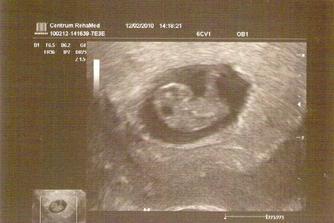

25. září čekáme miminko

Po jednou neúspěchu teď věříme v úspěch. Držte palce!